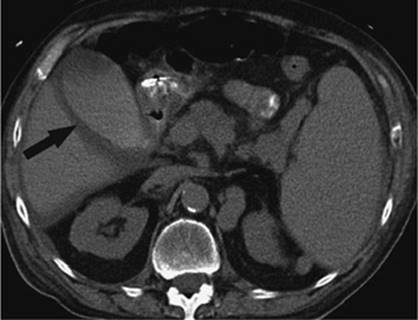

Figure 35.14. Failed endoscopic placement of common bile duct (CBD) stent due to the presence of a large mass (black arrow) within the CBD. (Image courtesy of James Caridi, MD.)